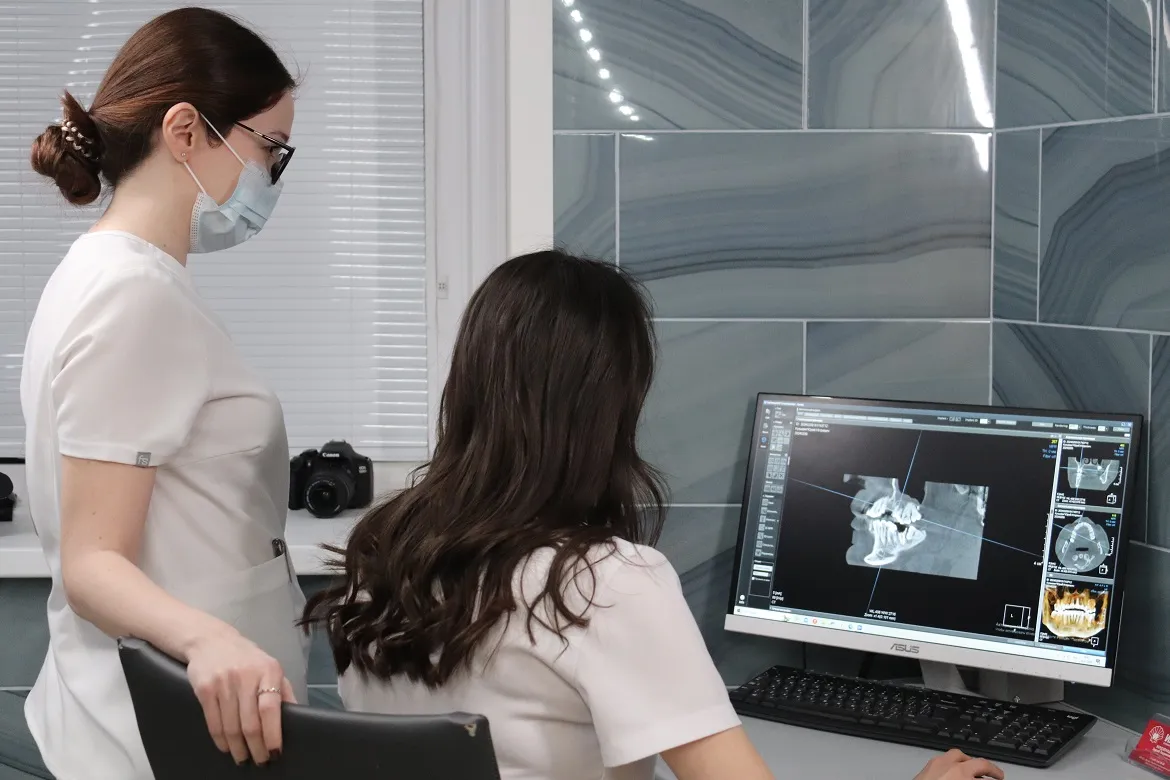

Бесплатная консультация и диагностика

Основная цель нашей клиники - качественная 3D-диагностика чтобы оценить состояние костной ткани и зубов пациента.